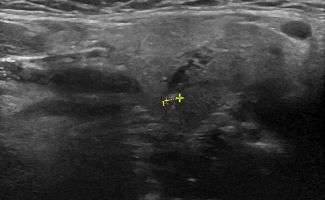

- Διάταση των εκφορητικών πόρων και εντοπισμό λίθων στα πλαίσια σιελολιθίασης και σιελαδενίτιδας

Η αξιοπιστία του Υπερηχογραφήματος στη διάγνωση παθολογίας των Σιελογόνων Αδένων έχει καθιερωθεί τα τελευταία χρόνια και εξασφαλίζεται με τη χρήση Υπερηχογράφων τελευταίας γενιάς με ειδικούς υψίσυχνους ηχοβολείς και με την εξοικείωση και εμπειρία του εξεταστή-ιατρού με την ηχοανατομία και παθολογία των Σιελογόνων Αδένων και της περιοχής κεφαλής – τραχήλου.